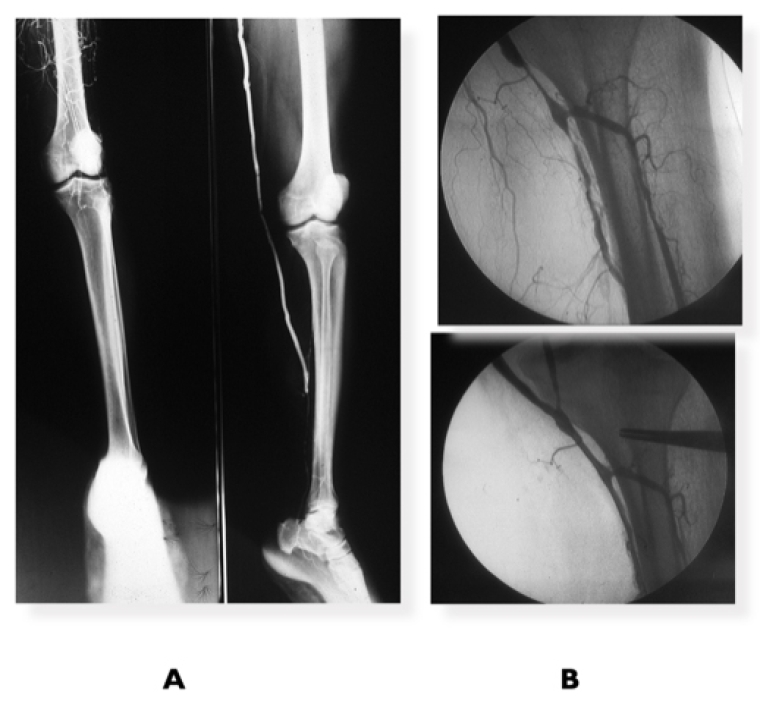

Guidance for revascularisation based on morphology and extension of disease where ER was the first option only for A and B lesions and OR/HyR for C and D lesions (Figure 1A) has radically changed. New and better guidewires for recanalisation of chronic occlusions, primary stenting and the use of covered stents for distal aorta and bilateral iliac occlusions have expanded endovascular options to complex lesions [12,13,14], including re-fashioning of new AI bifurcation – CERAB for covered endovascular reconstruction of aortic bifurcation - and complete AI occlusions (Figure 1B) with excellent geometrical reconstruction, prevention of thrombus fragmentation and migration through the bare stent cells and midterm and long-term outcomes comparable to OR. HyR with local endarterectomy with profundaplasty is useful to improve outflow especially in multi-segmental occlusive disease and/or severe stenosis of the profunda femoris and to provide an access (Figure 1C) for endovascular treatment of multi-segmental arterial disease.

Figure 1. Proximal revascularisation

A) Hybrid repair: iliac stenting + femoro-femoral crossover bypass for left external iliac stenosis plus right superficial femoral occlusion. B) CERAB for AI complete occlusion. C) Multilevel right common iliac treated by hybrid procedure: right common femoral artery endarterectomy and profundaplasty + iliac stenting and superficial femoral artery stenting for long occlusion.